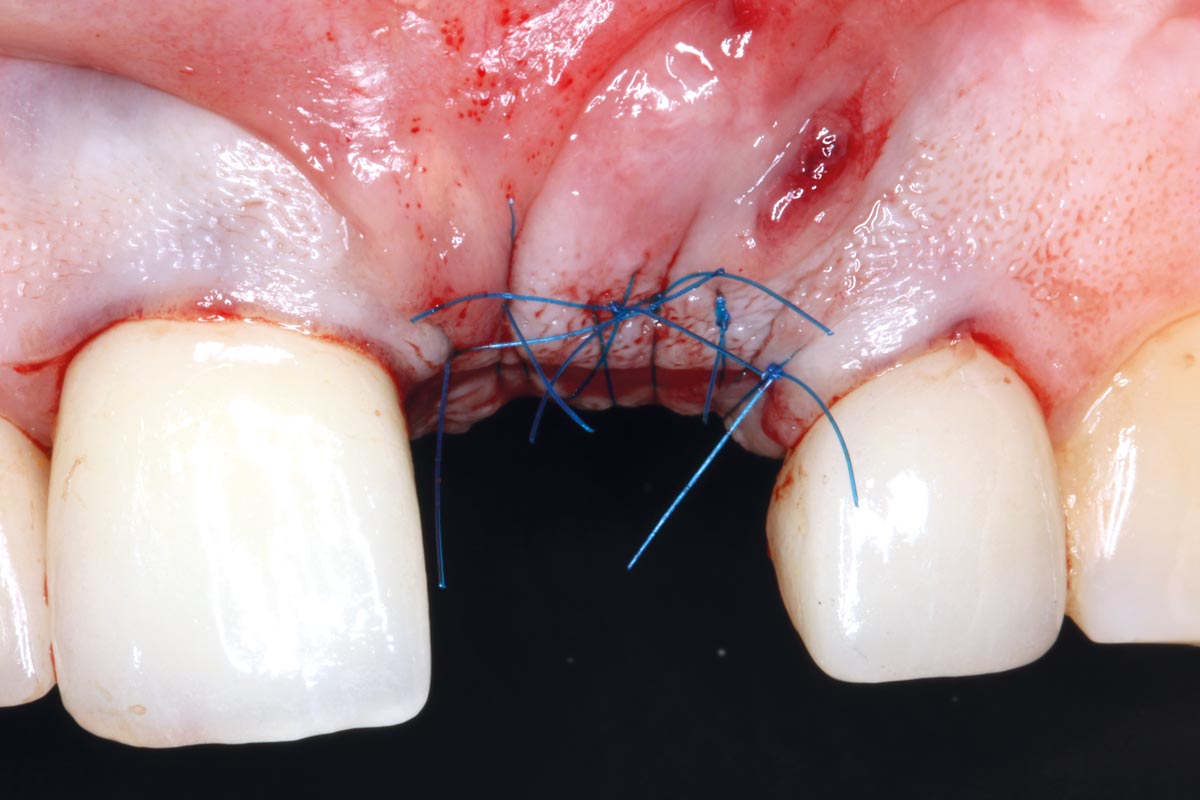

07/10 - Lateral view

Socket augmentation using mucoderm®, maxgraft® and Straumann® Emdogain® - Dr. A. Puišys